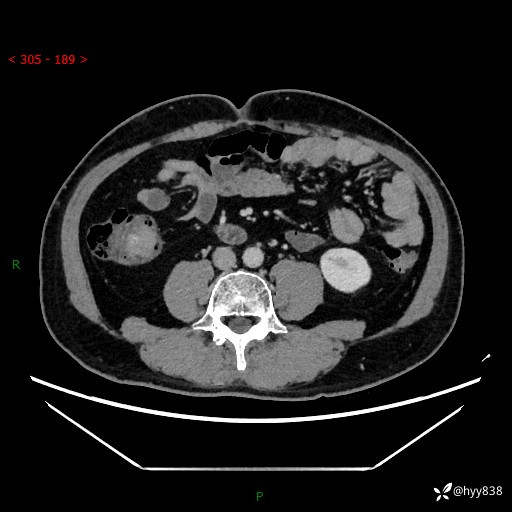

腹部CT增强扫描(外院CT平扫)

两期CT值:75hu 82hu